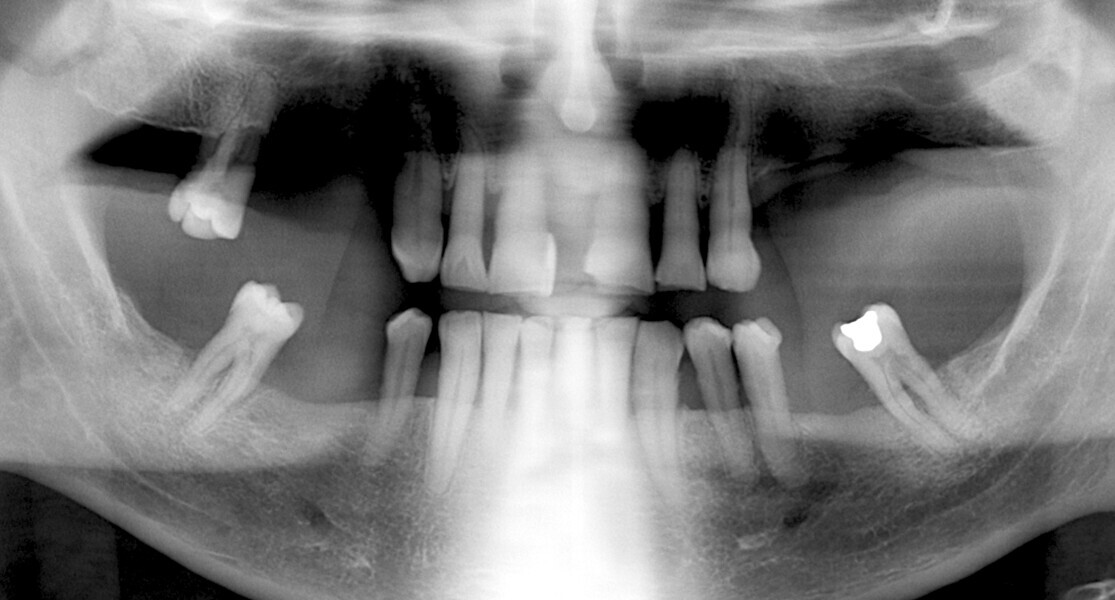

The fully digital Pro Arch protocol